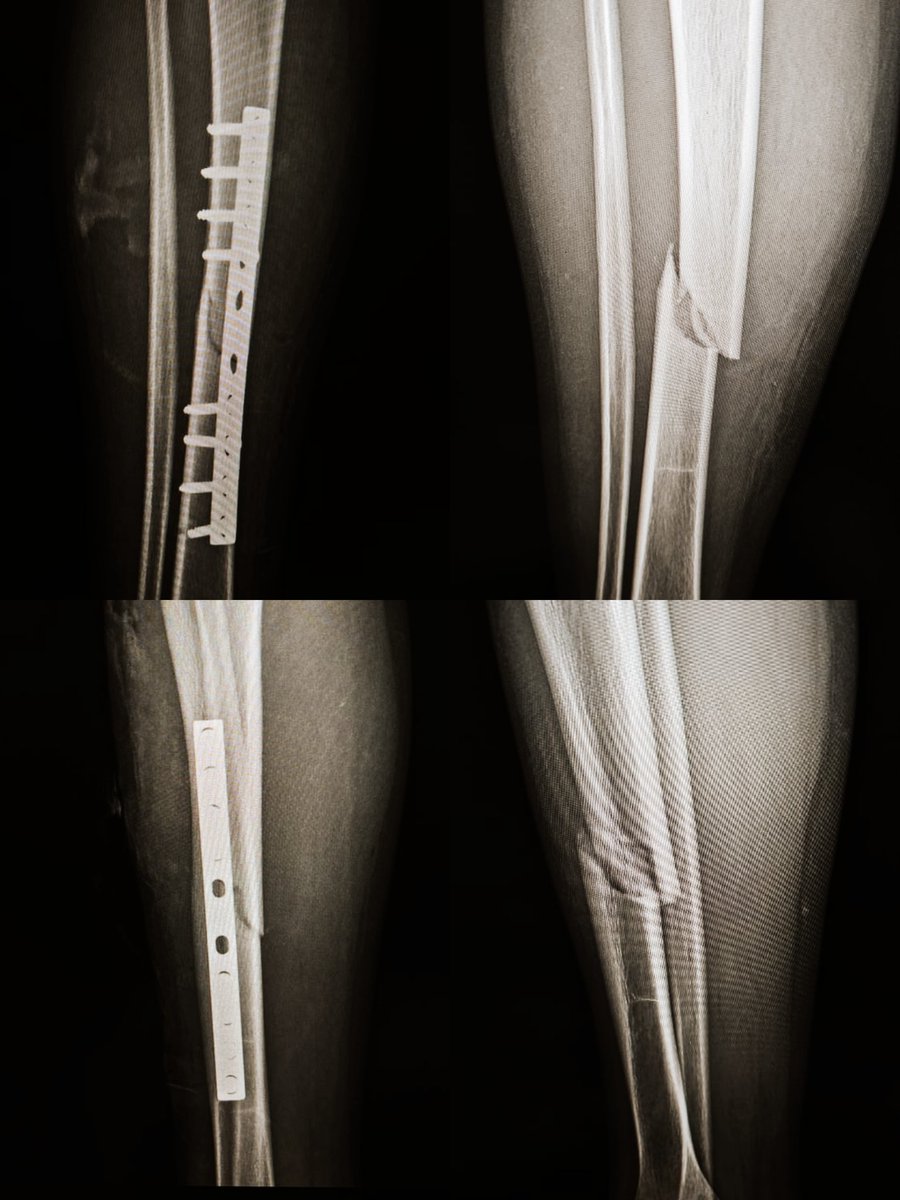

Another two cases.... "1st case" Male patient 17 yrs with fracture distal shaft both bones leg fixed by one third plate for fibula and Biological distal tibia locked plate for tibia. "2nd case" Male pt 37 yrs with fracture distal ulna fixed by Hooked plate.

Another two cases....

"1st case"

Male patient 17 yrs with fracture distal shaft both bones leg fixed by one third plate for fibula and Biological distal

tibia locked plate for tibia.